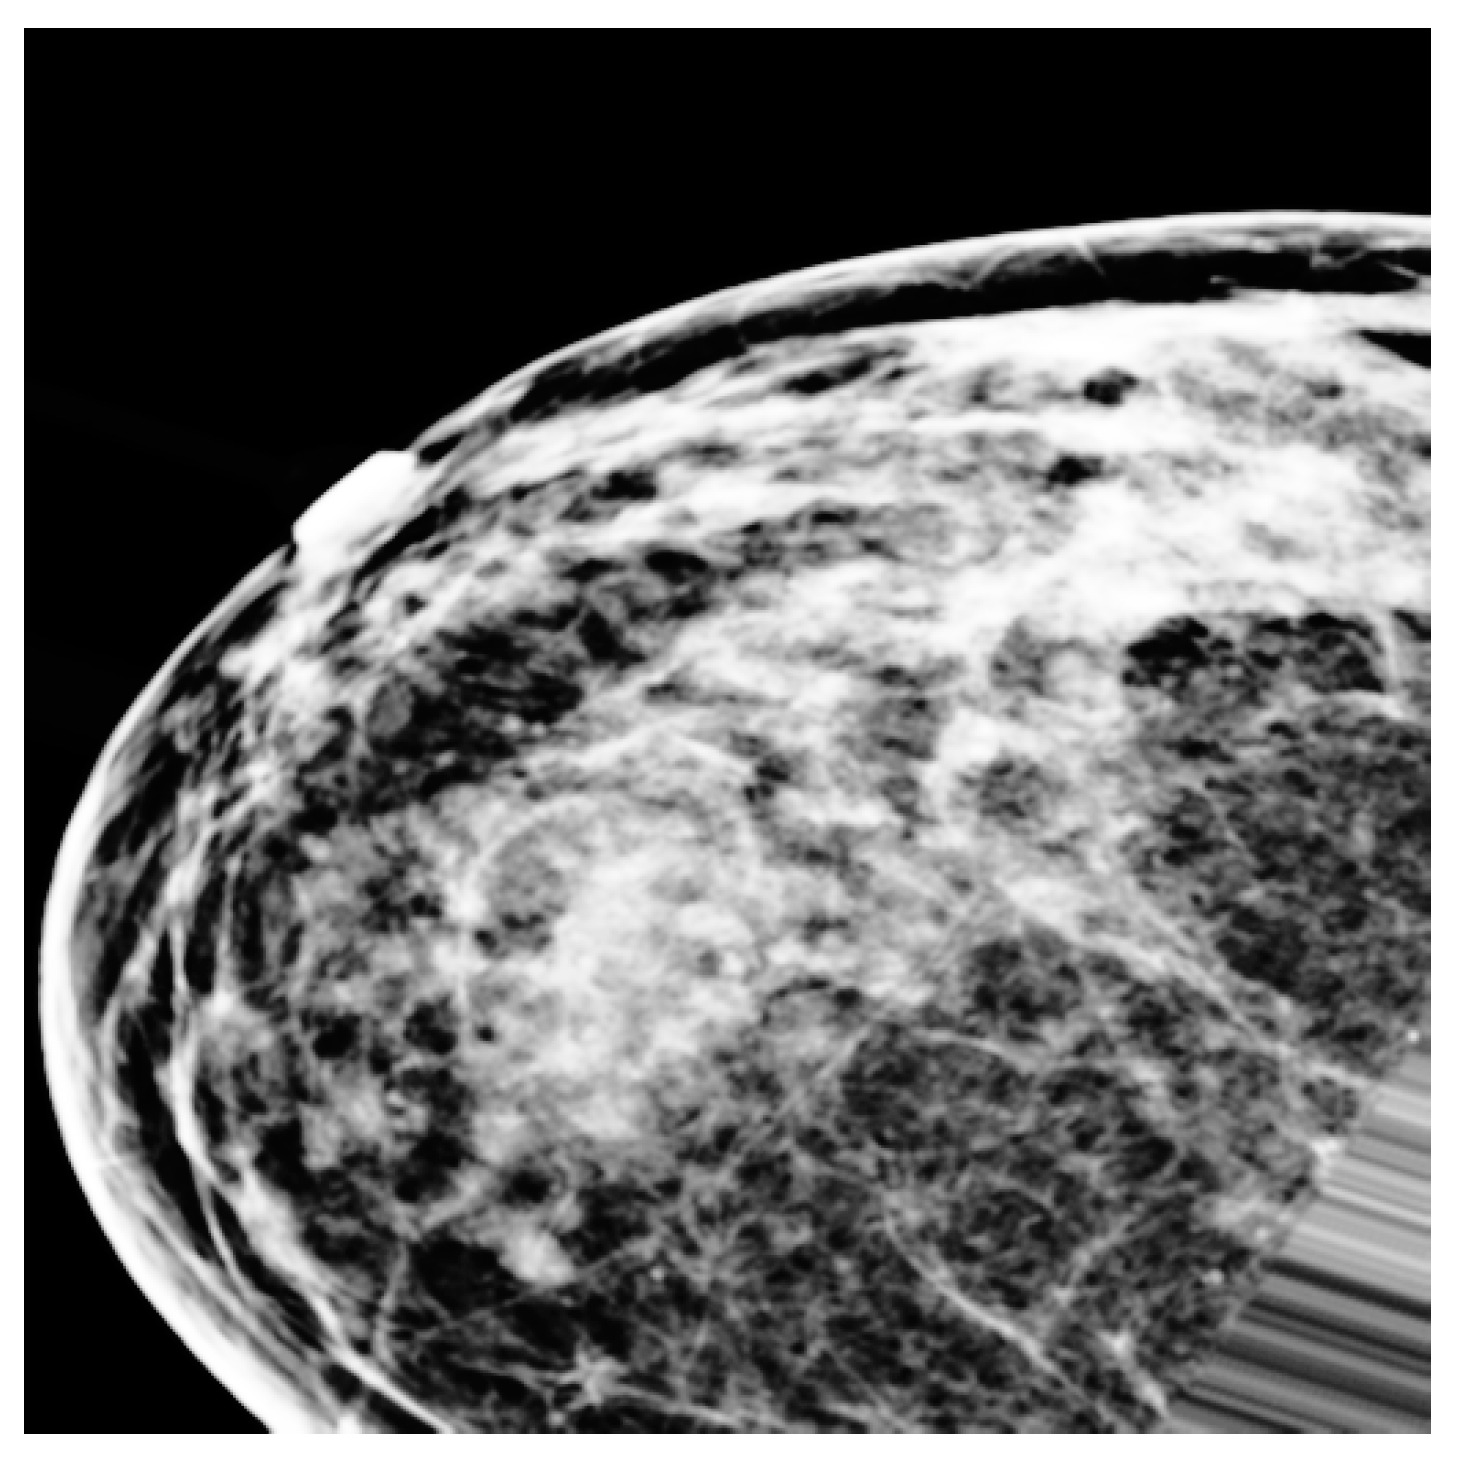

3.3. Preprocessing

3.4.5. Imbalanced Data Sampling Technique